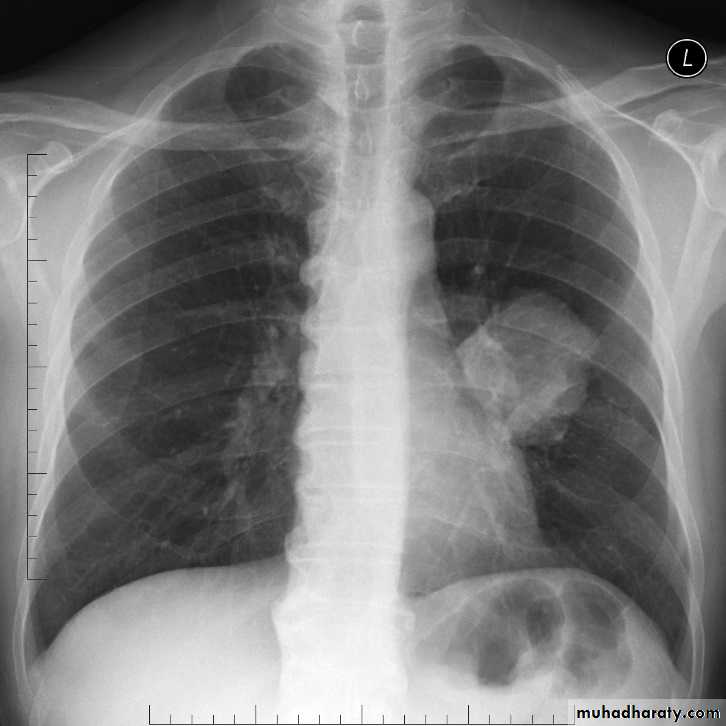

Pleural effusionX-ray of pleural effusion

Massive right effusion